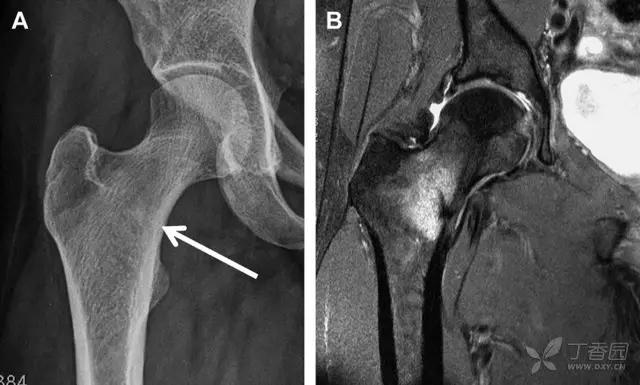

股骨颈骨折常发生在老年人,头下型骨折最常见,但是当股骨外旋或有明显的关节炎骨赘形成时,骨折较难发现。此外,肥胖和骨量减少增加髋部 X 片诊断难度,所以需格外注意。

因骨结构重叠影响,股骨转子骨折发生轻度移位时亦很难发现,加做一个不同角度的 X 线片有助于诊断(图 7)。

图 7 摔倒后股骨大转子骨折。A 正位片初步检查未发现明显骨折,进一步检查发现大转子上方皮质中断(箭头)。B 蛙式侧位片示骨折分离,尤其是后方(箭头)。初步检查时忽视了这一点,是因为股骨颈未能充分显示